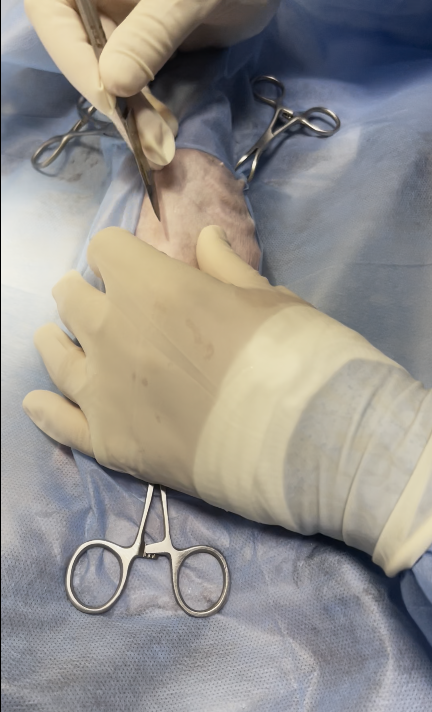

Surgical excision or partial hepatectomy is the treatment of choice.

in this case only biopsy sampling was obtained due to these reasons

owner was informed intraoperatively with :

lesion was close to major hepatic vessels & bile ducts, the risk of intraoperative bleeding or biliary leakage would be high, discouraging full lobectomy.

non-invasive, benign nature: conservative management was chosen instead of aggressive surgery

The cat’s advanced age (14 years) and possible comorbidities increased anesthesia and surgical risks

owners declined extensive surgery for risk reasons, opting for palliative management